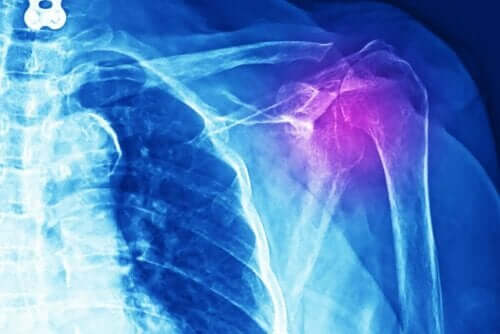

Det mest uppenbara tecknet på axeltendinit är inflammation och smärta.

En läkare måste göra olika tester för att diagnostisera denna typ av skada. Testerna kan bestå av röntgen, ultraljud, MRT eller datoriserad axiell tomografi (CT-skanning). Dessutom måste läkaren göra en medicinsk undersökning och en detaljerad genomgång av patientens medicinska historia.